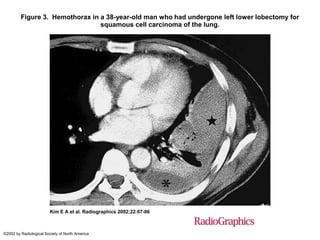

Figure 3. Hemothorax in a 38-year-old man who had undergone left lower lobectomy for

squamous cell carcinoma of the lung.

Kim E A et al. Radiographics 2002;22:67-86

©2002 by Radiological Society of North America